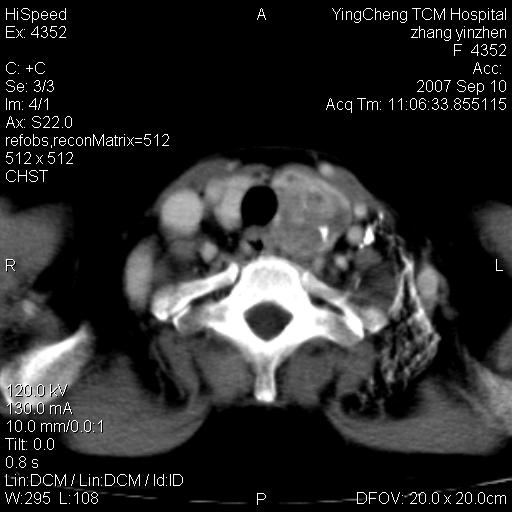

以下是引用卜一在2007-9-18 14:41:00的发言:[br]右肺肿块:毛刺+胸膜凹陷征+供血血管+浅分叶+强化。支持:周围性肺癌 !另:左侧甲状腺腺瘤!

以下是引用夏季在2007-9-18 11:00:00的发言:[br]1。右肺肿块,周围有短毛刺,肺门侧有血管与其相连,胸壁侧有胸膜凹陷征,考虑周围性肺癌 2。左侧甲状腺软组织肿块,内有高密度钙化灶,考虑左侧甲状腺腺瘤。